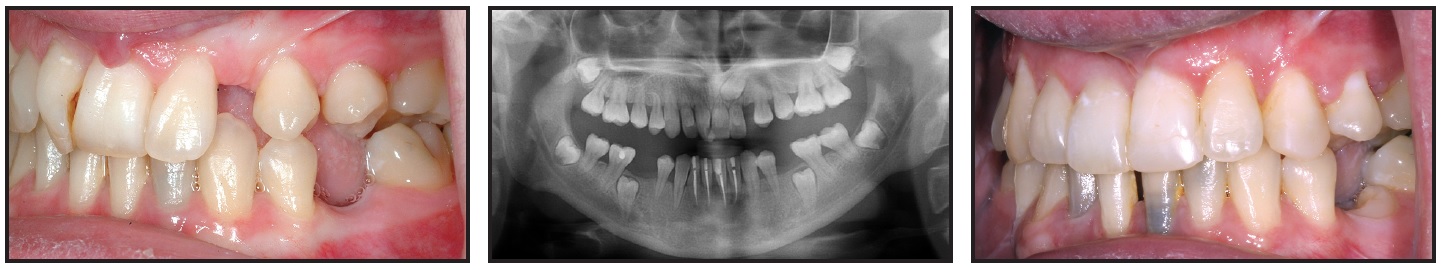

A 13-year-old male presented with the chief complaint that his upper teeth were too prominent (Fig. 1).

Fig. 1 13-year-old male patient with skeletal and dental Class II malocclusion and retrusive mandible before treatment.

He had skeletal and dental Class II relationships, with a retrusive mandible, a convex profile, and severely buccally inclined lower incisors (Table 1). Mild crowding was evident in the lower arch, and the dental midline was deviated to the right.